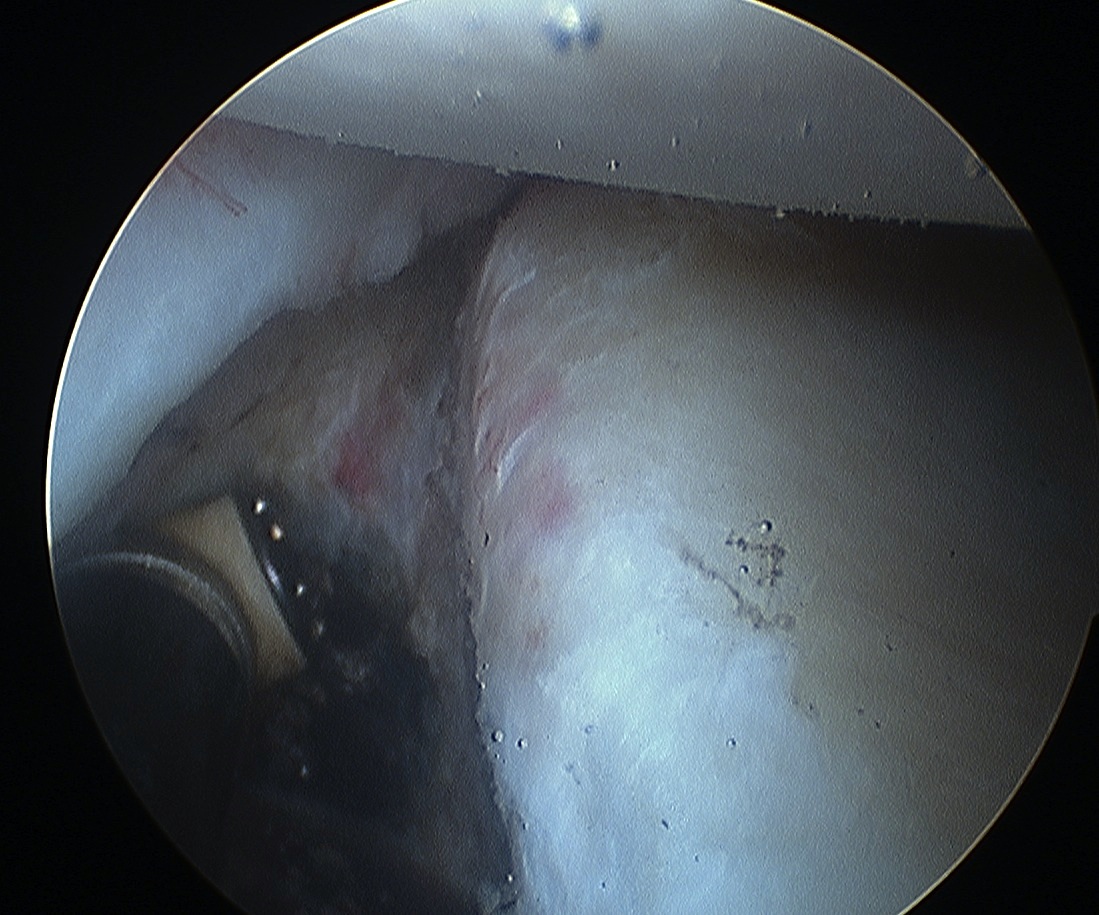

Shoulder Arthoscopy Bankart MobilisationShoulder Scope Bankart Mobilisation

Shoulder Stabilisation Anterior Labral MobilisationShoulder Stabilisation Anterior Labral Mobilisation 2